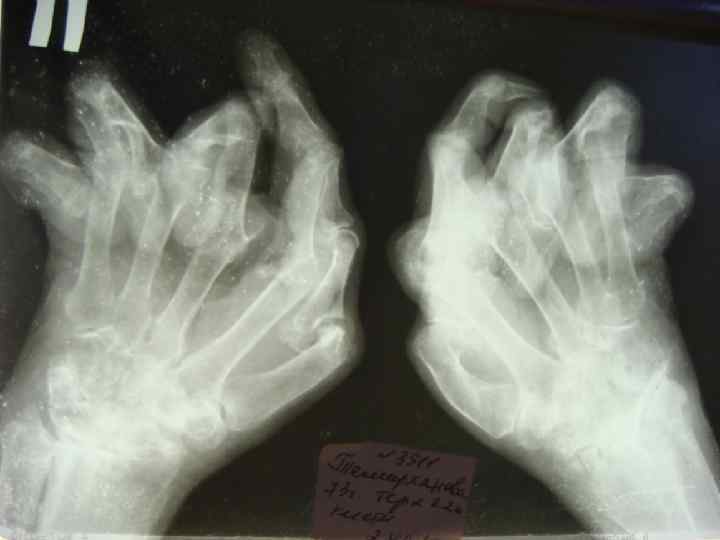

СТАДИИ ТЕЧЕНИЯ РА l l ЧЕРЕЗ 1 -2 ГОДА ВОСПАЛЕНИЕ СТИХАЕТ И НА ПЕРВЫЙ ПЛАН ВЫСТУПАЕТ ПРОГРЕССИРУЮЩАЯ ДЕФОРМАЦИЯ СУСТАВОВ ЗА СЧЕТ ПЕРИАРТИКУЛЯРНЫХ ТКАНЕЙ. ПРИЛЕЖАЩИЕ К СУСТАВАМ МЫШЦЫ АТРОФИРУЮТСЯ. ВСЛЕДСТВИЕ НАТЯЖЕНИЯ СВЯЗОК РАЗВИВАЮТСЯ СГИБАТЕЛЬНЫЕ КОНТРАКТУРЫ, НЕУКЛОННО НАРАСТАЕТ ФИБРОЗНОЕ, А ЗАТЕМ КОСТНОЕ АНКИЛОЗИРОВАНИЕ, ВПЛОТЬ ДО ПОЛНОЙ ФИКСАЦИИ СУСТАВА. ИЗ-ЗА УЛЬНАРНОЙ ДЕВИАЦИИ ПАЛЬЦЕВ РУК КИСТИ ПРИОБРЕТАЮТ ФОРМУ "ЛАСТ МОРЖА".

Характерная деформация кистей при РА

Ульнарная девиация кисти

Деформация кисти по типу "лебединая шея".

R-ЛОГИЧЕСКИЕ СТАДИИ РА (STEINBROCKER, 1949) l СТАДИЯ I — ОКОЛОСУСТАВНОЙ ОСТЕОПОРОЗ БЕЗ l СТАДИЯ II — НЕЗНАЧИТЕЛЬНОЕ СУЖЕНИЕ l СТАДИЯ III — ЗНАЧИТЕЛЬНОЕ РАЗРУШЕНИЕ ХРЯЩА И l СТАДИЯ IV — ПРИЗНАКИ III СТАДИИ + АНКИЛОЗ ДЕСТРУКТИВНЫХ ИЗМЕНЕНИЙ. СУСТАВНОЙ ЩЕЛИ, ЕДИНИЧНЫЕ УЗУРЫ КОСТЕЙ. КОСТИ: ВЫРАЖЕННОЕ СУЖЕНИЕ СУСТАВНОЙ ЩЕЛИ, МНОЖЕСТВЕННЫЕ УЗУРЫ, ПОДВЫВИХИ, КОСТНЫЕ КИСТЫ.